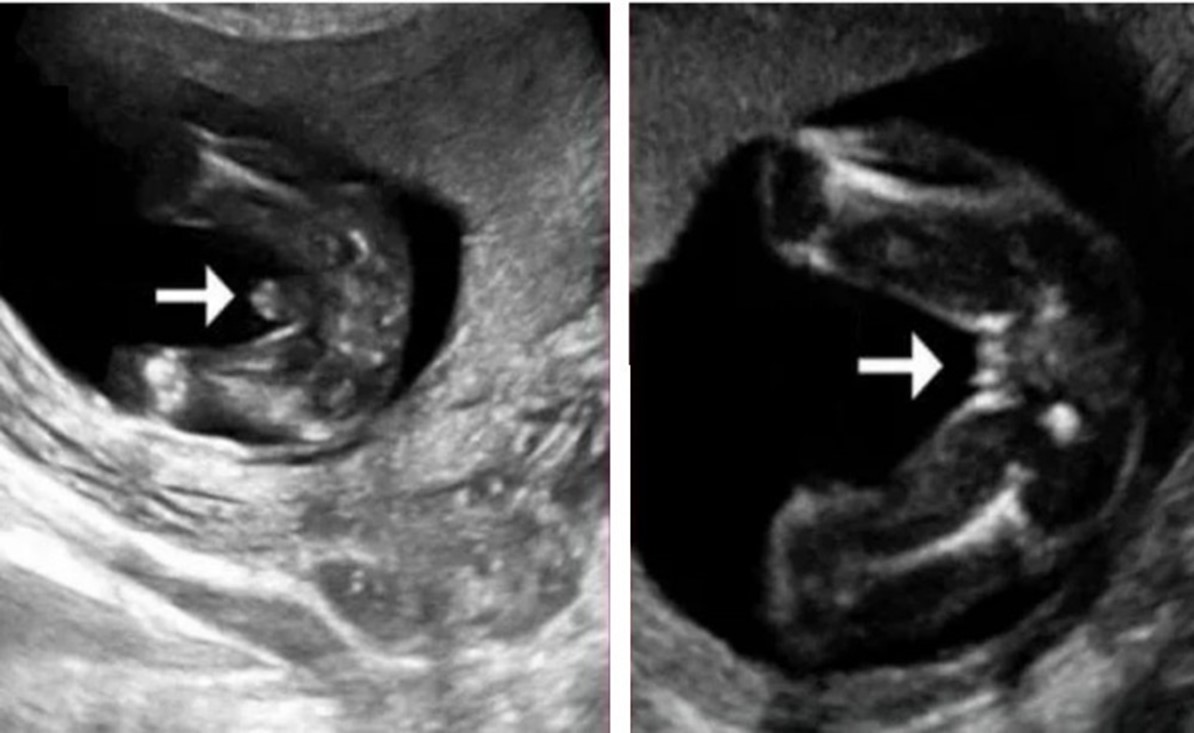

Пол на 14 неделе беременности по узи

Пол на 14 неделе беременности по узи 88 фото